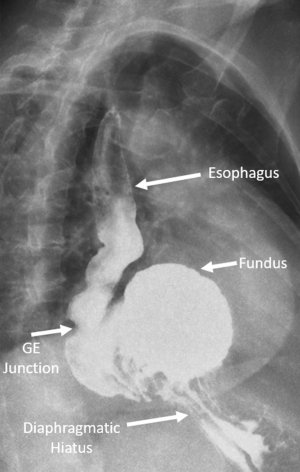

The main components of a diagnostic work-up and characterization of PEHs are a contrast swallow study and EGD. Chest X-rays may reveal a lucency in the retrocardiac space indicative of herniated stomach (see Figure 1) or pneumonia indicative of aspiration and these abnormalities are often the first clue to diagnosis. A chest X-ray alone, however, is not typically adequate in the work-up, as the differential diagnosis includes a mediastinal cyst, abscess, dilated/obstructed esophagus or other type of diaphragmatic hernia. CT scans of the chest and abdomen are helpful to understand the extent of herniation, accurately measure crural separation, and may be important in the acute setting. However, they are not always necessary in the elective setting, with contrast swallow studies and EGD being commonly used (12). Contrast swallow studies help classify the type of hernia by delineating the location of the GE junction and showing the extent of herniated stomach (see Figure 2). They can also help identify functional abnormalities of the esophagus, such as poor peristalsis or tertiary contractions, and may reveal reflux (either spontaneous or provoked).